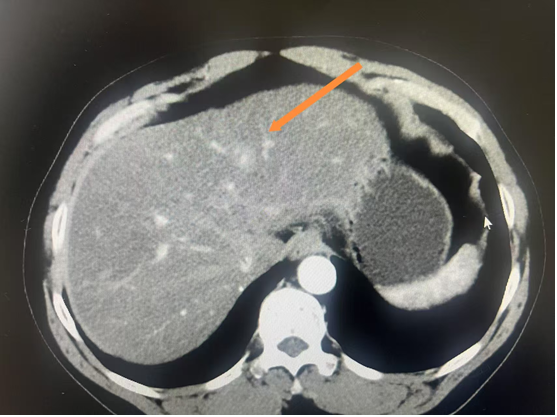

7. 肝脏肿瘤射频消融

B超定位射频消融治疗小肝癌